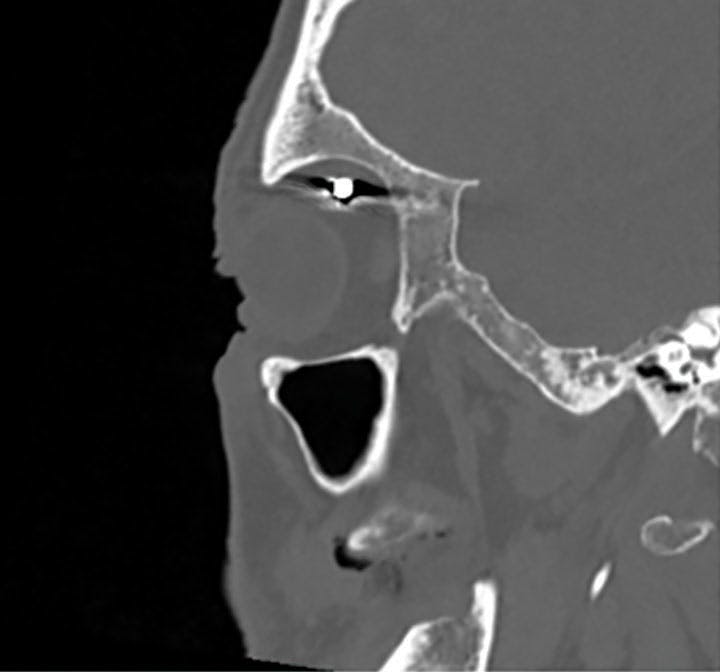

Fundoscopy showed a temporal subretinal hemorrhage accompanied by discrete vitreous hemorrhage in the vicinity, as well as Berlin macular edema (Figure 1). No tears or signs of retinal detachment were noted. A CT scan of the orbits detected the presence of a metallic foreign body adjacent to the lateral wall with no signs of retrobulbar hemorrhage or damage to the globe or extraocular muscles (Figure 2). The surgeons who observed the foreign body opted for conservative course, and thus, it was not removed from the orbital cavity at this time.